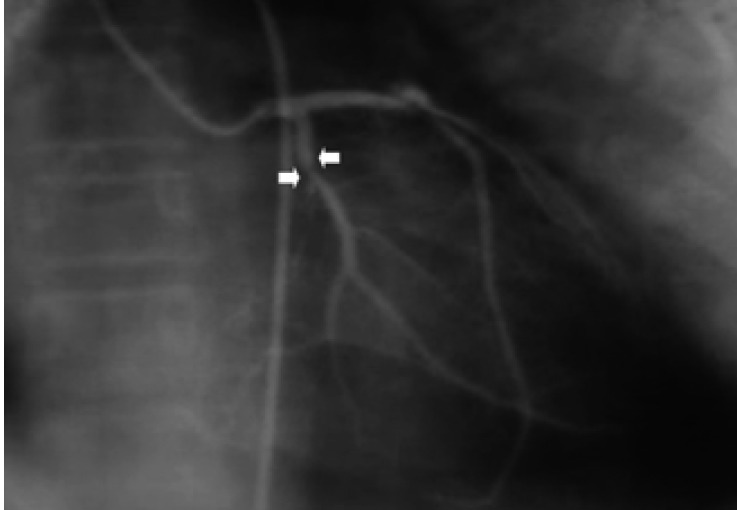

Figure 1

Left coronary angiogram with 80% stenosis on the proximal portion of the left circumflex (arrow).